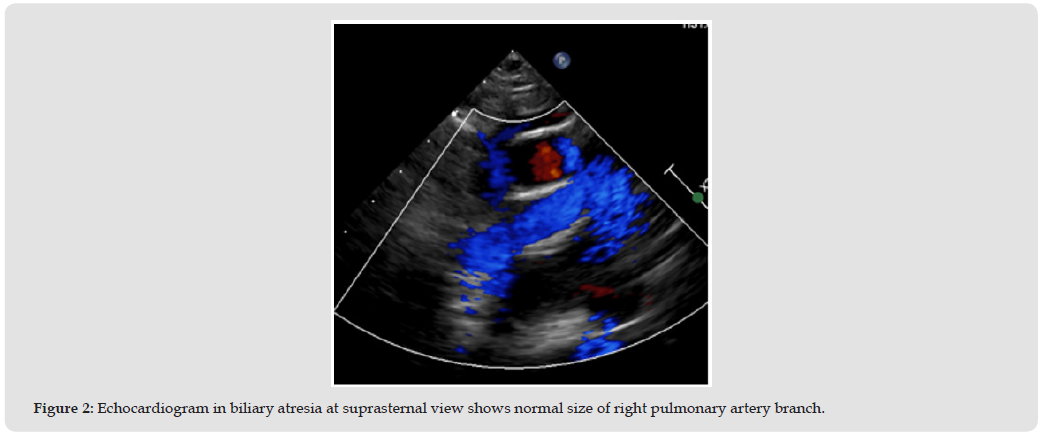

In patients with hepatomegaly, the apical 4 chambers angle is easier to perform and provides a clearer echocardiography image (Figures 1 & 2). This is because of two reasons:

1. These children are usually underweight, and have thin chest walls, which makes it not difficult to examine the apical area. The transducer can send ultrasound waves to the heart.

2. In hepatomegaly case, the liver pushes the heart 1-2 intercostal spaces higher than normal, which pushes the apex closer to the wall too [3] Although CT or MRI are the standard equipment for demonstrating pulmonary branch structure in long segment.

But the better property of echocardiography consist of inexpensively, non-invasively, portability and radiation safety, promote echocardiography popular equipment of imaging [4]. The Alagille syndrome and biliary atresia or liver cirrhotic most often cause patients to have liver enlargement [5] This condition is an obstacle to echocardiography in the parasternal area because it will cause the apex to be raised, resulting in difficult images adjust. This condition is also a limitation of examination in the subcostal view, Because the liver is enlarge and the tissue changes, it has a hard appearance, making it impossible to apply pressure to produce a clear image. [6] (Figure 3) The angiogram was used in case of need evaluated pulmonary hypertension and the role of intervention. (Figure 4).